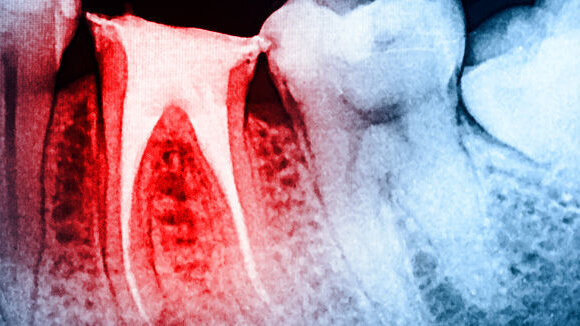

Un equipo de investigadores ha determinado que un sistema rotatorio de níquel-titanio (NiTi) con un movimiento recíproco produce el mayor cambio volumétrico en el tercio apical del canal radicular. Además, el sistema tuvo el tiempo de preparación más rápido de los tres que se probaron.

Los sistemas evaluados en el estudio fueron ProTaper Universal (Dentsply Sirona), el sistema de un solo instrumento RECIPROC (VDW) y el sistema rotatorio K3XF (Kerr Dental). Para evaluar las características de conformación de cada sistema, los investigadores simularon 30 canales radiculares con una curvatura de 60° en un bloque de resina transparente (Endo Training Bloc, Dentsply Sirona). Los canales tenían una longitud de 16,5 mm y una sección recta de 10 mm antes de la curva. Cada bloque fue asignado aleatoriamente a uno de los tres grupos de instrumentos.

Los investigadores utilizaron tomografía microcomputarizada para la evaluación tridimensional de la capacidad de conformación de los instrumentos, el transporte del canal, el cambio volumétrico y la capacidad de centrado, así como los parámetros geométricos básicos de la morfología interna del diente.

Encontraron que RECIPROC produjo mejors cambios volumétricos apicales en los canales, en comparación con ProTaper Universal y K3XF. Por el contrario, el sistema K3XF mostró menos transporte y una mejor capacidad de centrado a 2 y 3 mm del agujero apical que los otros dos sistemas. Sin embargo, no hubo diferencias significativas en la relación de centrado y transporte entre ProTaper Universal y RECIPROC.

Aunque el tiempo de preparación del canal fue el más corto con RECIPROC, esto puede haber sido porque, siendo un sistema de un solo instrumento generalmente requiere menos tiempo de instrumentación, señalaron los investigadores. En general, todos los instrumentos formaron los canales simulados sin ningún error de conformación significativo, concluyeron.

El estudio, titulado "A comparison of the shaping ability of three nickel-titanium rotary instruments: A micro-computed tomography study via a contrast radiopaque technique in vitro", se publicó en línea en la revista BMC Oral Health.